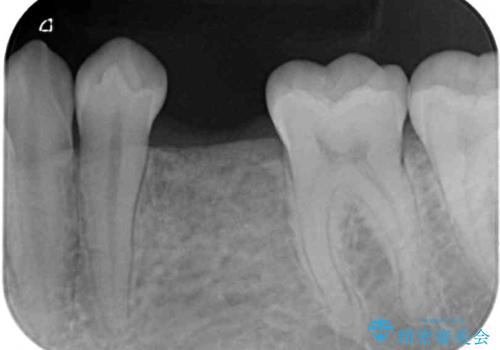

左下には後続永久歯の欠損した乳歯が残存しており、叢生を相まって咬合関係が乱れていました。

乳歯は抜歯し、インビザラインにて矯正治療を行いながら、並行してインプラントによる補綴治療を行うこととしました。